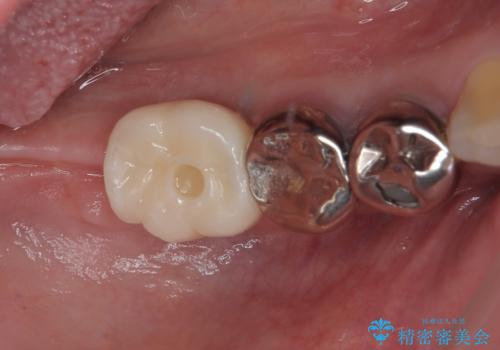

金属の詰め物が取れた オールセラミッククラウン

担当医 有澤哲郎